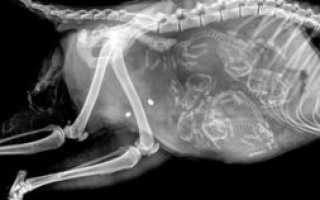

На рентгене хорошо просматриваются кости и позвоночник. Шерсть уже полностью сформирована. В целом на 50-й день котята уже готовы к рождению, но данный момент также зависит от породы.